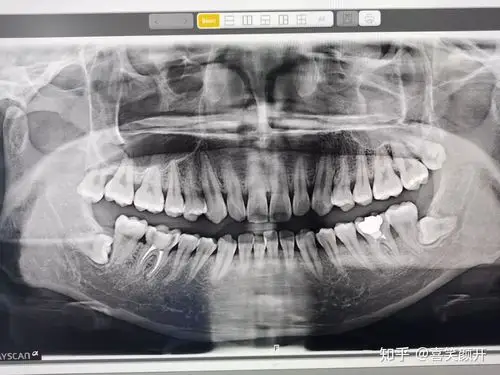

重新拍了牙科ct之后,医生钻开之前在县城医院补上的材料,牙齿已经严重